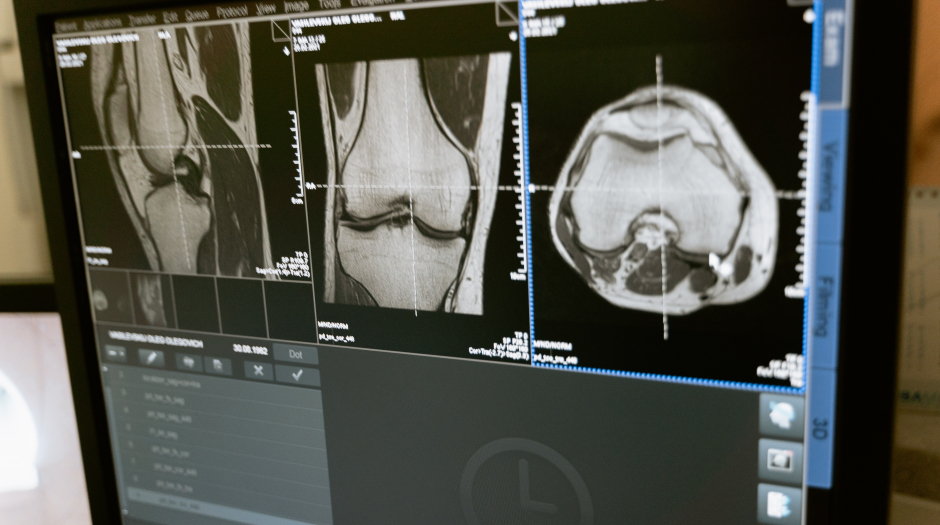

Procedures are performed by an Interventional Radiologist who is a trained specialist and techniques are performed under the guidance of a variety of imaging modalities including Xrays, Ultrasound, CT and MRI. The use of local anaesthetic is favoured over general anaesthetic which provides patients with a degree of pain relief and less risk as compared to general anaesthetic usage. Owing to its minimally invasive technique, procedures are performed through a small incision made at the targeted site.